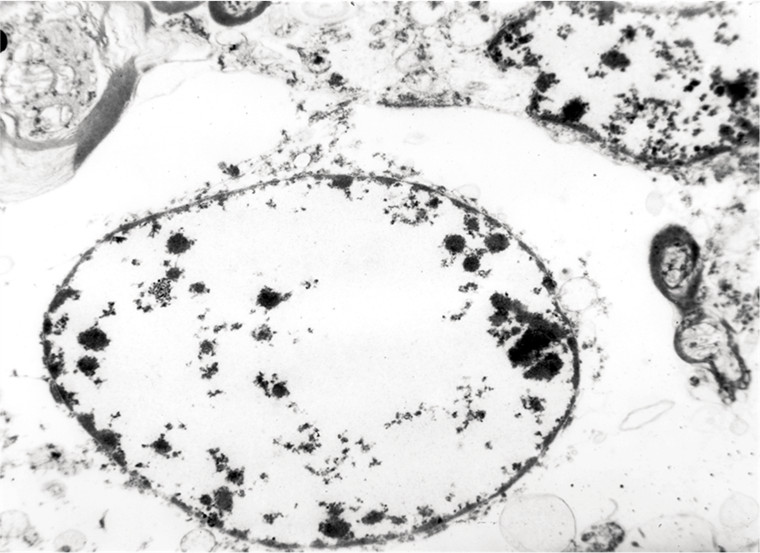

W encefalopatii wątrobowej w wyniku obniżenia poziomu glutaminianu, następuje uszkodzenie morfologiczne pewnego typu komórek OUN. Zmienione morfologicznie komórki nazywamy komórkami Alzheimera typu II, zwanymi także „nagimi jądrami”. Zmiany te dotyczą następującego typu komórek: